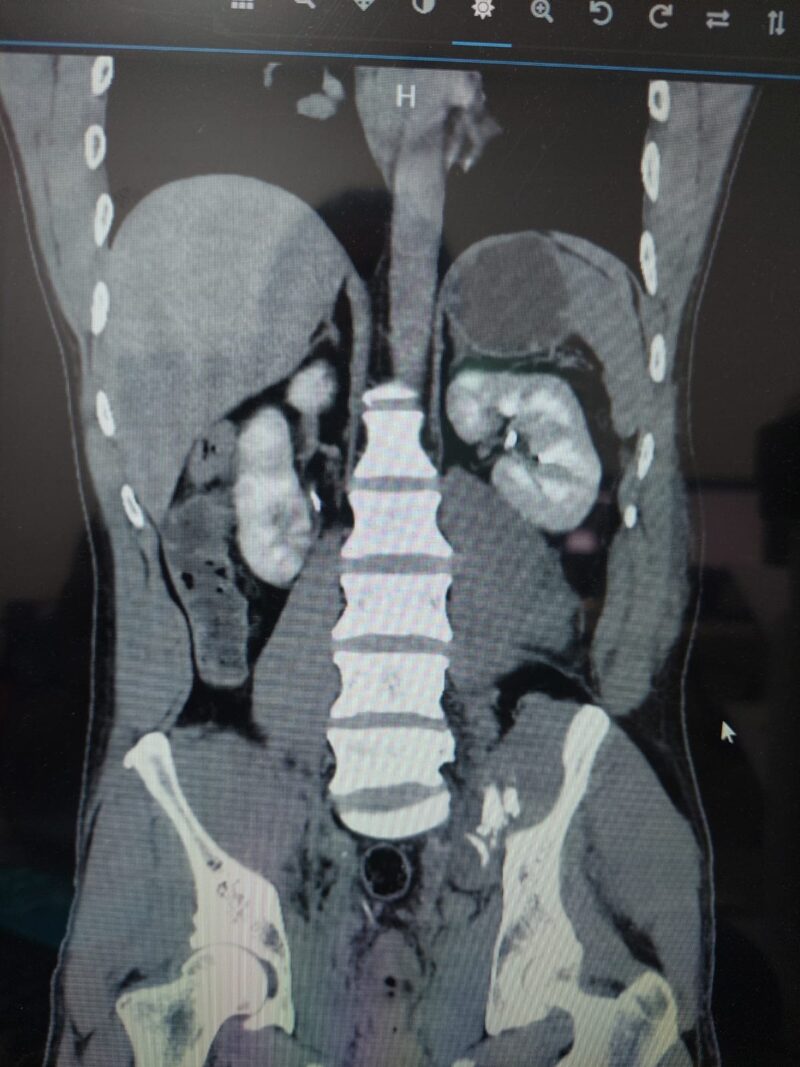

El Servicio de Angiografía del hospital Escuela “Gral. José F. de San Martín” cuenta con un equipo de alta complejidad que permite hacer diagnóstico y tratamiento de enfermedades vasculares, ya sea del sistema arterial periférico o del sistema venoso. También pueden tratar pacientes con trauma y con procesos hemorrágicos de cualquier parte de la economía humana.

La intervención de esta área, se realiza además en caso de “trauma o enfermedades neurológicas de alta prevalencia y mortalidad, como aneurisma cerebral o accidentes de tránsito con politraumatismo”.